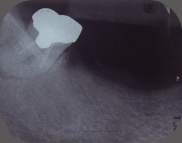

通常のレントゲン写真(デンタル・パントモ)は2次元画像なので、正確な骨の幅や量、さらには神経の位置を把握することができません。

そのため、当院では必ず術前に3次元画像であるCT撮影を行い、インプラントを埋める位置の骨の状態を精査します。

この際に診断用ステントを取りつけて撮影を行います。

撮影したCTデータをもとに「Simplant」という画像診断ソフトを使い、骨量・骨幅、骨密度、さらには神経や上顎洞の正確な位置を把握します。

それらの情報をもとに、治療前のシュミレーションを行い、どのサイズのインプラントをどの角度で埋入するかを決定します。